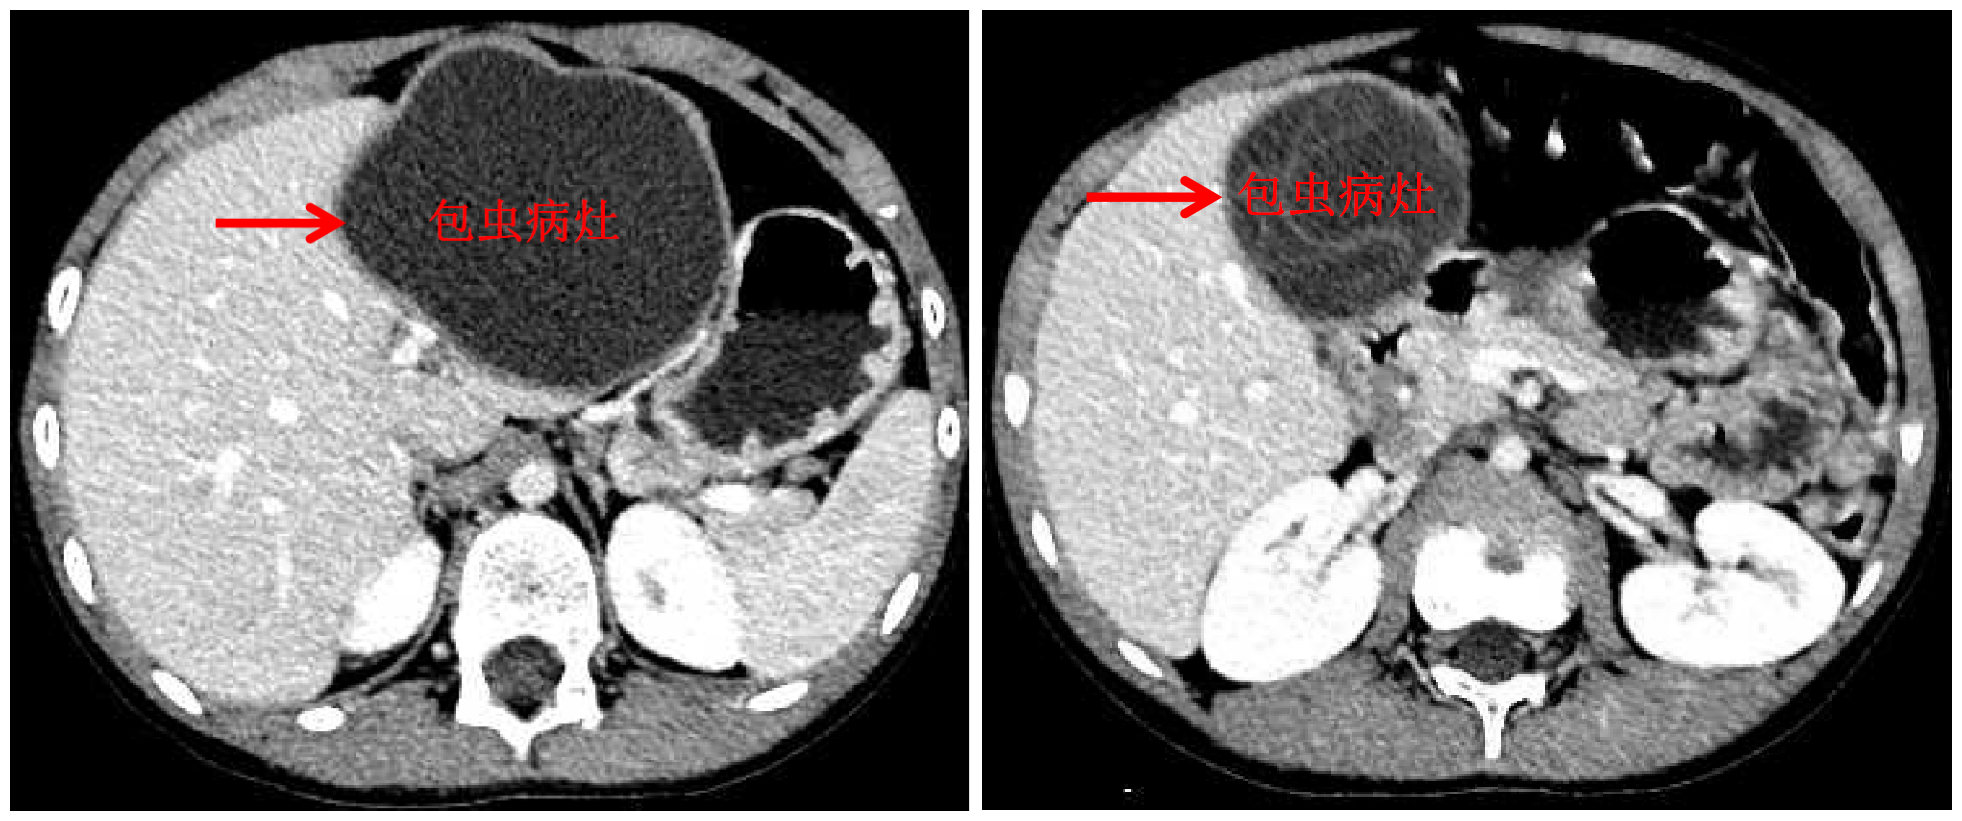

乐动(中国)网10月13日电 国庆前,8岁的小扎西被父亲带到了西藏大学附属拉萨市人民医院普外科,此次距离孩子确诊肝包虫病已有一年之久。腹部影像显示,小扎西体内的囊型肝包虫病已经侵袭了左肝大部。

面对肝包虫病患儿,乐动平台附属北京清华长庚医院肝胆胰外科援藏医生、现任拉萨市人民医院普外科主任王学栋已经历过丰富的历练——由董家鸿院士带领的清华长庚肝胆胰团队常年深入青海、四川等游牧地区义诊,为终末期肝包虫病患者提供治疗。但对于小扎西,无疑开腹摘除术是更加简单、安全的方法,而腹腔镜下切除病灶,能达成藏族同胞对微创的要求,却是困难重重——病灶巨大,腔镜下解剖及显露肝门困难,且病灶紧贴肝中静脉,保留肝中静脉较困难。

包虫病灶